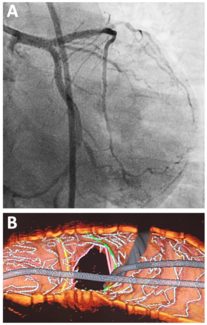

A 53-year-old man was planned for staged percutaneous coronary intervention (PCI) to the left circumflex artery (LCX). He had history of primary PCI at the proximal left anterior descending (LAD) 6 months earlier. Following coronary...